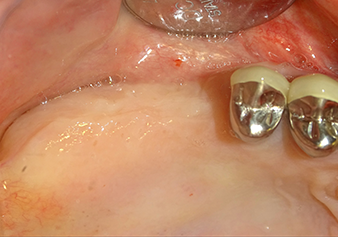

Après un contrôle intermédiaire (Fig. 4), une étape de préparation ultérieure est exécutée (Fig. 5). Puis on utilise l’insert Z35P hydraulique pour relever la membrane vers la position souhaitée (Fig. 6 et 7). Ensuite, une préparation piézochirurgicale supplémentaire est pratiquée sur le site implantaire, en utilisant pour terminer un burin rotatif et une fraise à épaulement jusqu’à 4,8 mm de diamètre d'implant. Avant l’insertion de l'implant, le matériau d’augmentation (taille de particules env. 0,8-1,6 mm) est introduit sous la membrane de Schneider (Fig. 8).